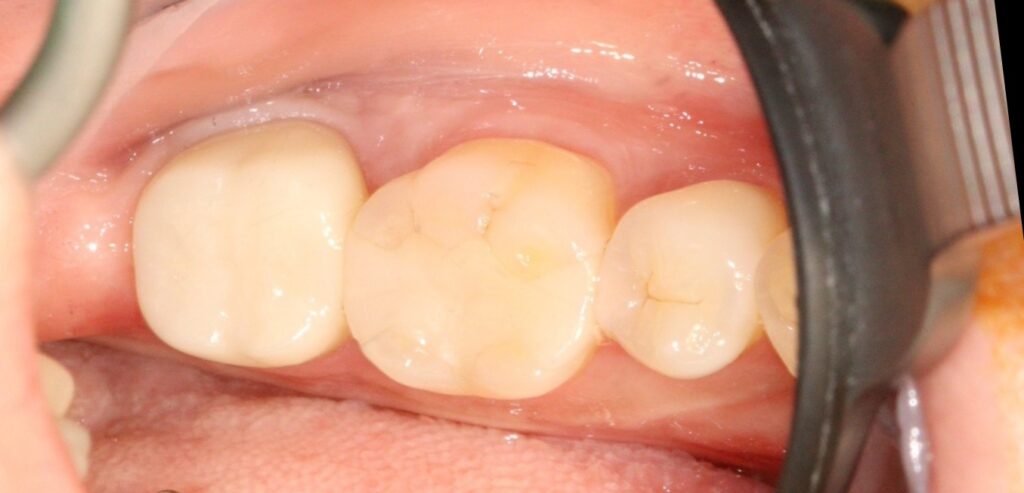

구강 내 모습을 확인해 보면

금니 치료한 어금니에

과거에 신경치료를 받은 후

금관을 씌운 상태인 것으로 확인됩니다.